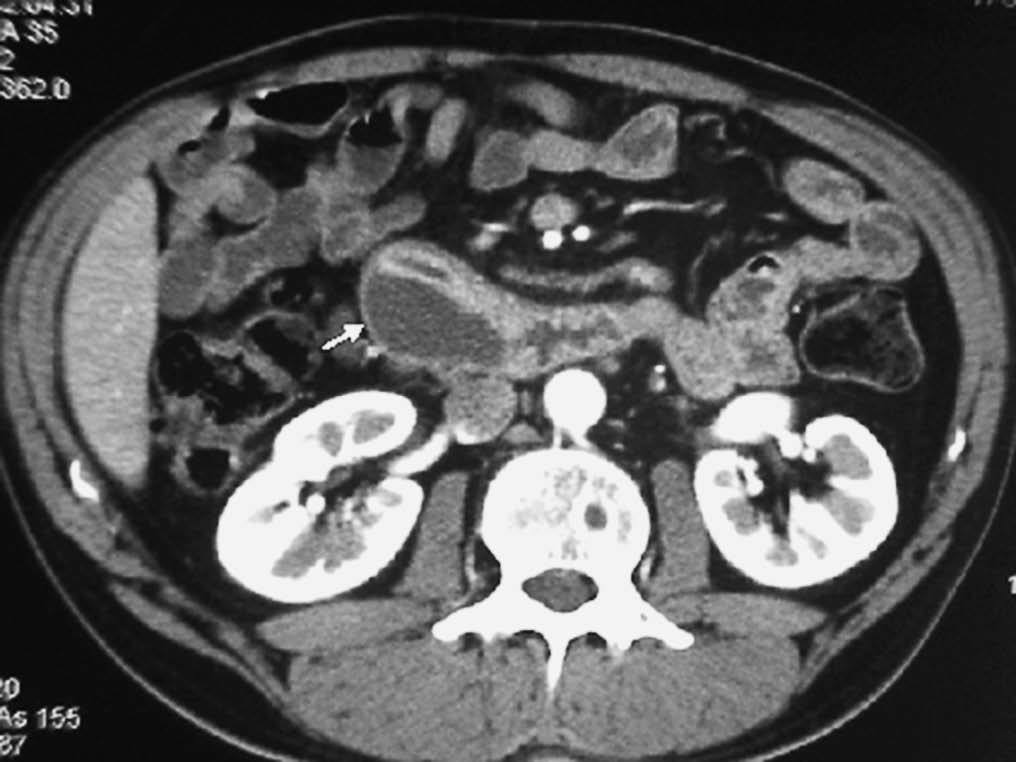

El linfoma intestinal también asienta con mayor frecuencia en el íleon. Aparece como un engrosamiento de pared, a veces nodular, que puede ser focal o difuso, que característicamente no produce estenosis de la luz intestinal, pudiendo producir una dilatación aneurismática del segmento afectado. La presencia de adenopatías viscerales o retroperitoneales, así como esplenomegalia puede sugerir el diagnóstico (fig. 20)22,24. Los tumores estromales malignos pueden alcanzar un tamaño considerable, apareciendo en la TC como masas heterogéneas con zonas internas hipodensas, debido a su tendencia a la necrosis y hemorragia, con realce periférico de contraste. Los malignos pueden invadir órganos vecinos, diseminarse al peritoneo o dar metástasis hepáticas, pero no suelen asociar adenopatías21,25,26.

Fig. 20--Linfoma duodenal. (A) Ecografía. (B) Tomografía computarizada con contraste intravenoso que muestra un engrosamiento circunferencial de la pared duodenal (D) con adenopatías mesentéricas y retroperitoneales (flechas).